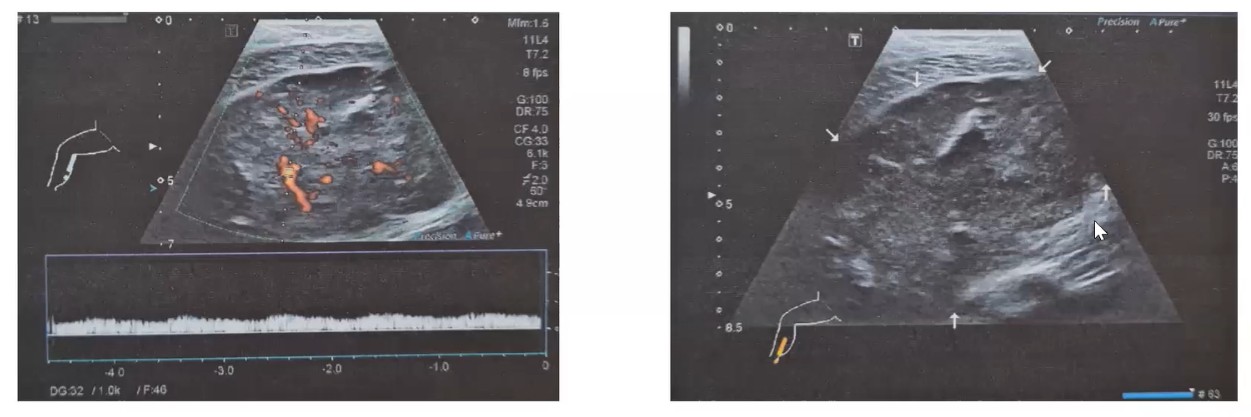

USG con toma de biopsia: se reporta tumor ocupativo en músculo gastrocnemio de 10.2x5.5 cm, de bordes regulares y con aparente cápsula, de consistencia sólida-heterogénea y de predominio hipoecoico. Al aplicar Doppler color con vascularidad intralesional. Se realiza biopsia con aguja de corte.